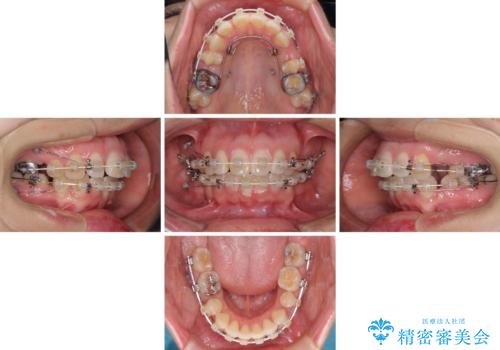

- 矯正装置

- 審美装置

- 2年10ヶ月

- 10-30回